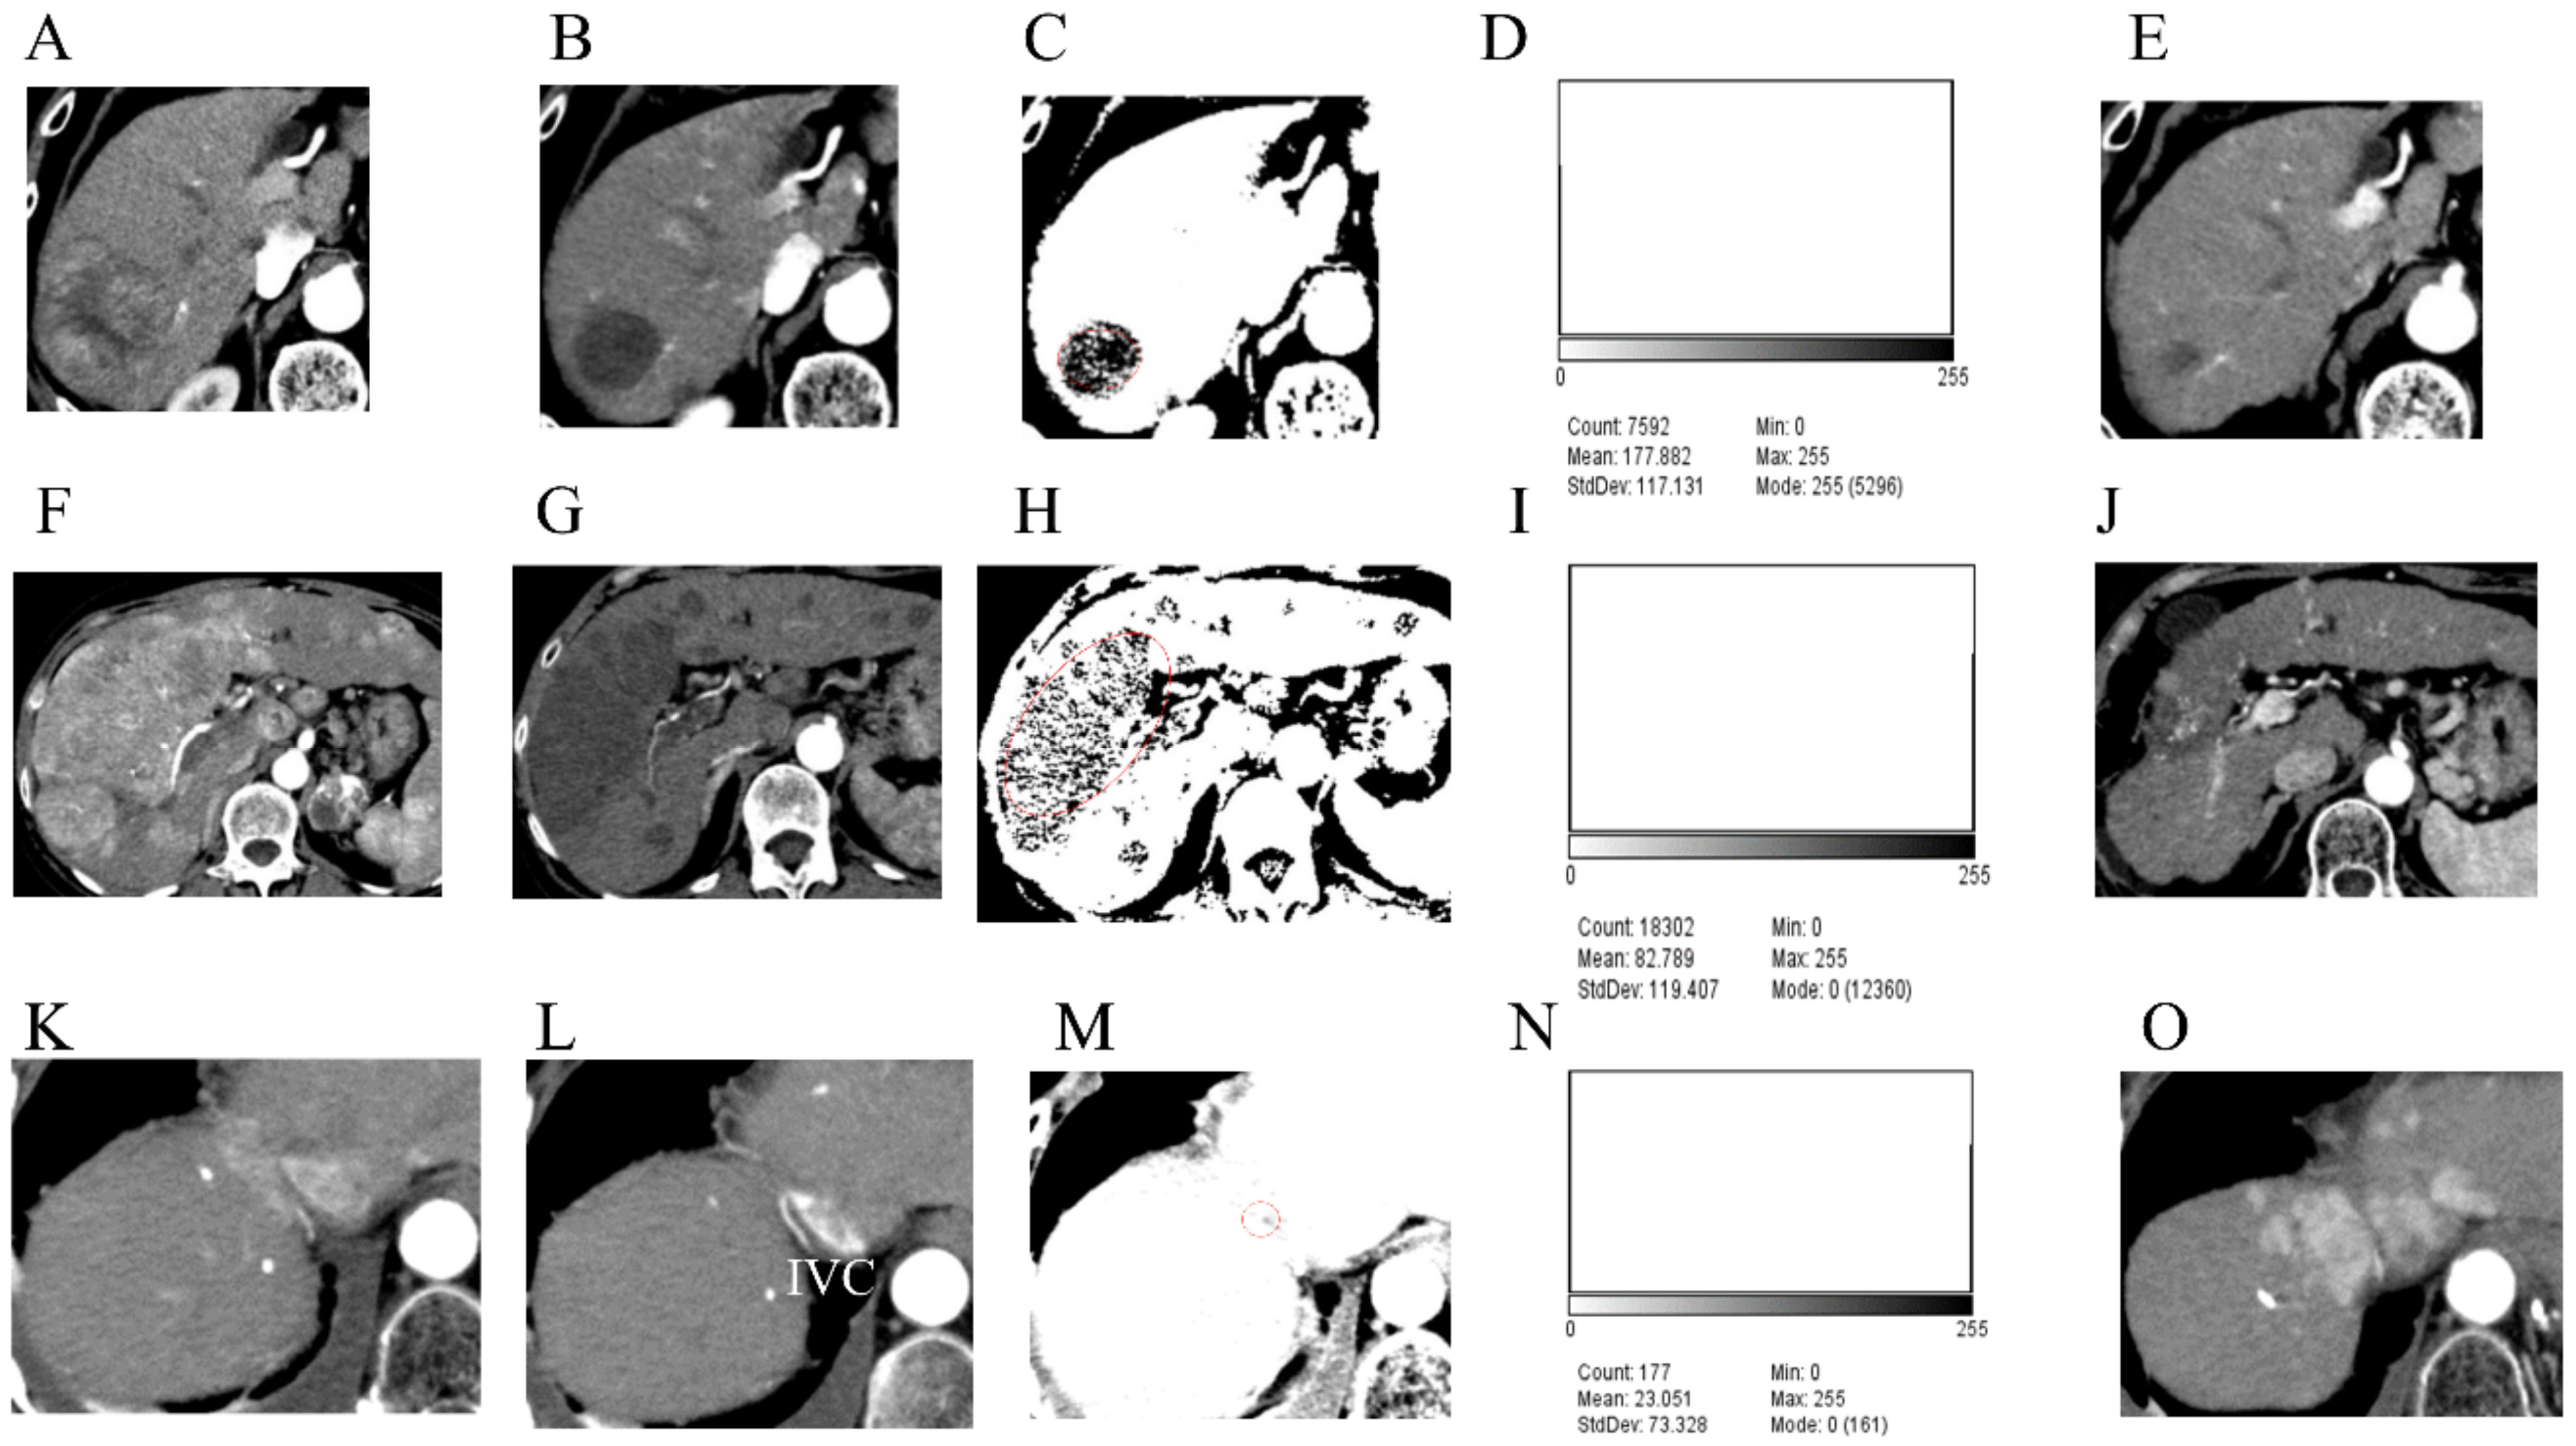

3.4. Case Presentations